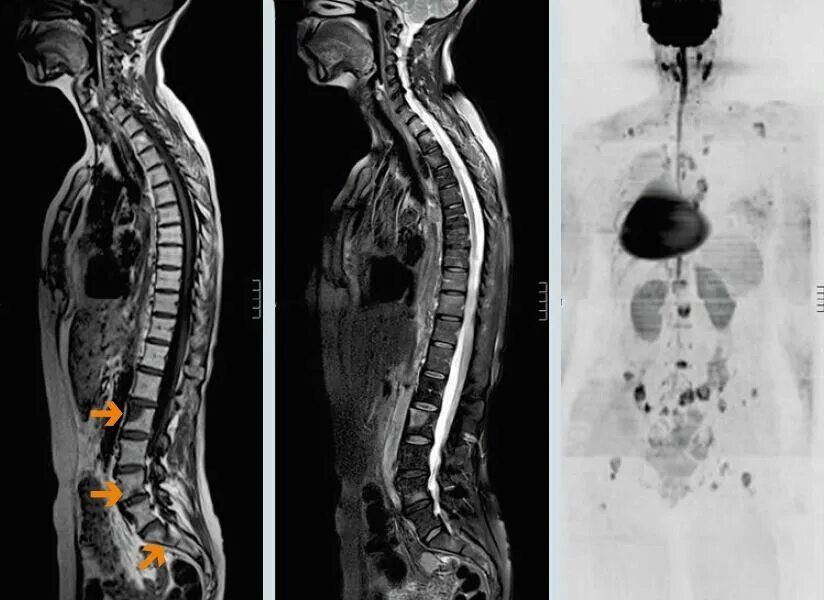

Симптомы рака позвоночника грудного отдела